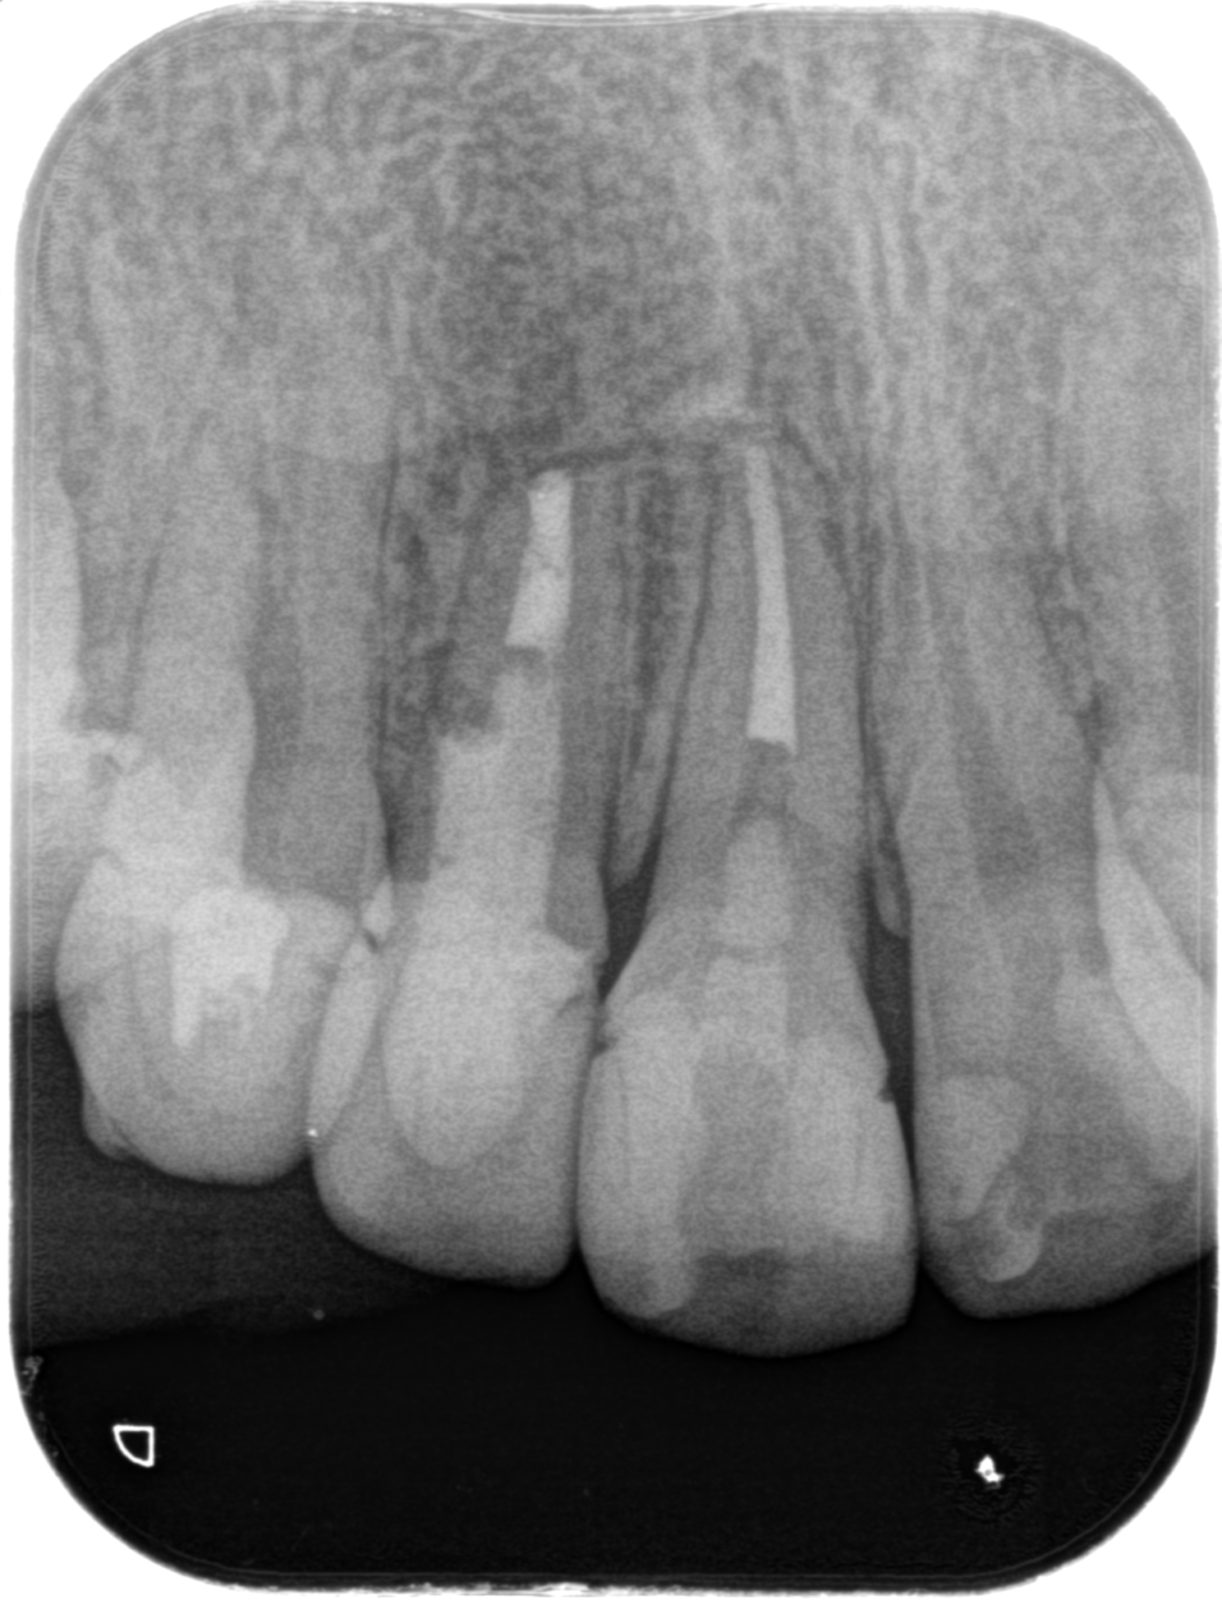

• 治療前

• 治療後

主訴右下の奥歯が冷たいものでしみる、何もしなくてもズキズキする

どのように治療したのかの具体的な説明当院の歯内治療専門医による根管治療(抜髄) NiTiファイル用いて根管を拡大形成、根管洗浄したのちにバイオセラミックシーラー(MTA系)を用いて根管充填、支台築造

治療期間治療開始から二回の来院で処置終了。間は一週間あける。一回の治療は約一時間半程度

治療費14.3万円 (上部構造は別)

その治療をすることで起こり得るリスク一般の保険医による治療に比べるとはるかに可能性は低いが、歯が薄くなるので破折のリスクが上がる